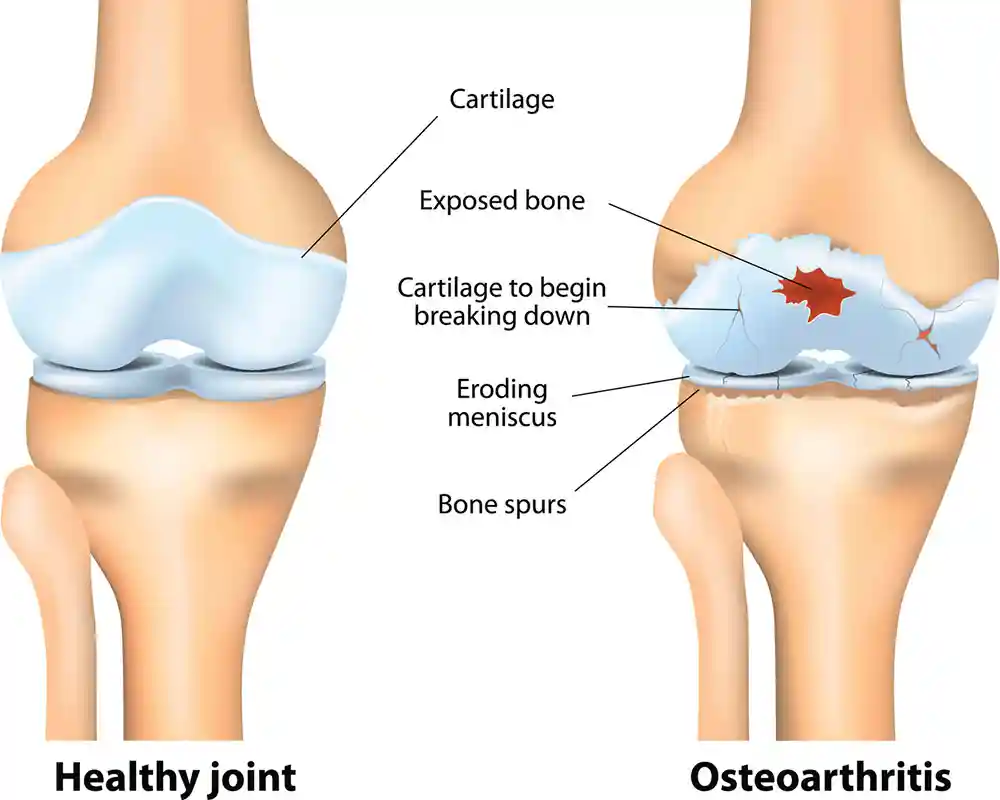

The knee must absorb significant mechanical forces. Two types of cartilage are vital for this:

Menisci: Fibrous pads that distribute axial load, absorb shock, and increase stability.

Articular Cartilage: A smooth, lubricated surface that reduces friction between abutting bones.

OA develops as these layers wear down. Over time, the menisci wear thin, reducing joint space and increasing friction on the articular cartilage. This leads to pain, decreased mobility, and often the growth of osteophytes (bone spurs).